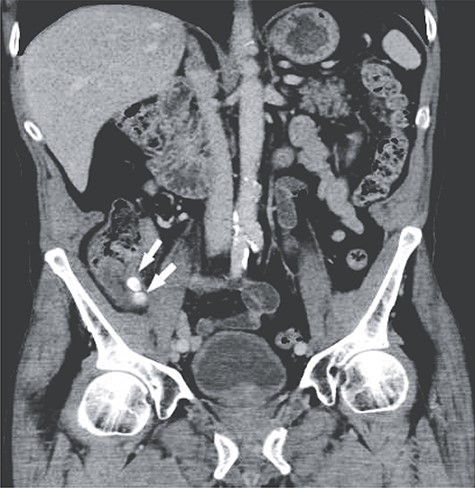

A 66-year-old male patient who had undergone bilateral blepharoplasty 3 days earlier was referred to our acute care surgical service with a 24-hour history of increasing right lower quadrant pain accompanied by nausea, vomiting and anorexia. Clinically he was found to be afebrile with a soft abdomen and focal tenderness at McBurney’s point. Significant laboratory investigations revealed a leukocytosis of 13.0. A CT scan of the abdomen confirmed the diagnosis of appendicitis with an impacted appendicolith at the appendicular outlet and a number of additional appendicoliths distributed along the length of the appendicular lumen (Figs 1–2). The patient was surgically consented for a laparoscopic appendicectomy with intraoperative video recording. At laparoscopy an inflamed and focally necrotic appendix was located coiled over the cecum (Figs 3–4). The appendectomy was completed without complication, and the specimen longitudinally transected in the operating room prior to pathological submission. This revealed four appendicoliths within the lumen, all measuring over 5 mm at their smallest diameter (Fig. 5). Pathology confirmed acute suppurative appendicitis with transmural necrosis, with the appendicoliths described as faeculent in origin. The patient’s post-operative recovery was uneventful.

Intraoperative picture demonstrating the inflamed and coiled appendix with signs of transmural necrosis.